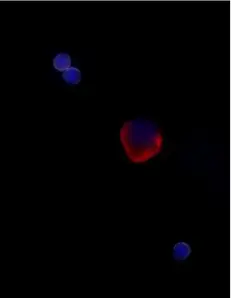

Example images from patient blood samples

Cluster of WBCs and epithelial CTCs - prostate

Cluster of EMT CTCs - prostate

Examples of Portrait+ CTC staining kit samples